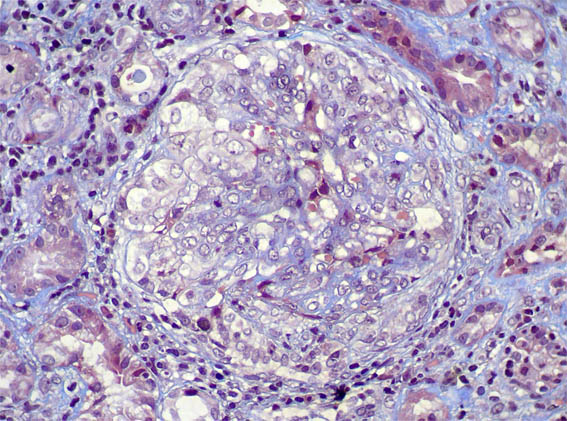

Figure 8. Masson's trichrome stain, X400.